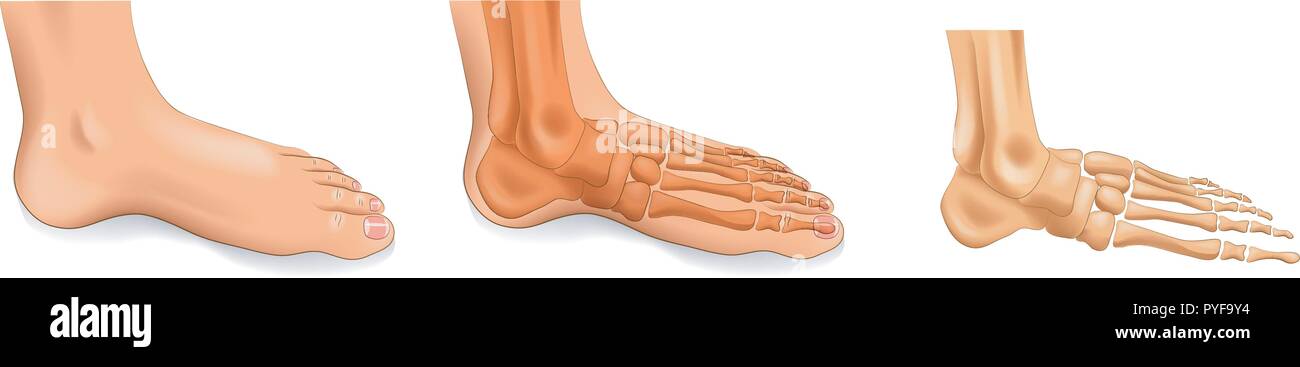

RF2J65WT4–Anatomie du pied. Pied humain avec le nom et la description de tous les os et sites. Vue de dessus et vue latérale. Arcs des pieds. Anatomie du squelette. Vecteur

RF2R3WKY1–Illustration médicale des principales parties des os du pied en vue latérale, avec annotations.

RF2X200ED–L'anatomie de l'articulation de la cheville. Région talocrurale ou os sauteur. Partie du corps humain où le pied et la jambe se rencontrent. Fascia plantaire et tendon d'Achille